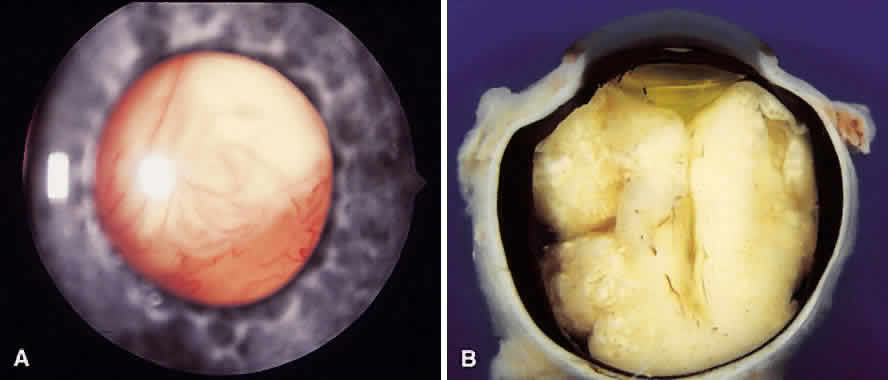

Retinoblastomas have been divided macroscopically into two groups, endophytic and exophytic. Endophytic tumors appear to originate in the internal nuclear layers of the retina and extend into the vitreous cavity, where they can readily be seen with the ophthalmoscope (Fig. 7). This is a common pattern. An exophytic tumor arises in the external nuclear layer. It may grow into the subretinal space and consequently detach the retina (Fig. 8). Palazzi and associates32 reviewed the histopathology of 297 enucleated eyes from patients with unilateral retinoblastoma and discovered some interesting correlations. They stated that positive family history was seen in the endophytic type more than the exophytic type. Also, they found that glaucoma and choroidal invasion occurred more often in the exophytic type.

Fig. 7. A. Advanced endophytic retinoblastoma with floating, white retinoblastoma tumor seeds in the vitreous. (Courtesy of Carol L. Shields, MD) B. Cross section of an enucleated globe demonstrating a massive endophytic retinoblastoma. (Courtesy of Carol L. Shields, MD, and Ralph C. Eagle Jr, MD, Philadelphia, PA.)

Fig. 8. A. Massive exophytic retinoblastoma with total retinal detachment. (Courtesy of Carol L. Shields, MD) B. Cross section of an enucleated globe with the posterior cavity filled by a large exophytic-type retinoblastoma. (Courtesy of Carol L. Shields, MD, and Ralph C. Eagle Jr, MD, Philadelphia, PA.)